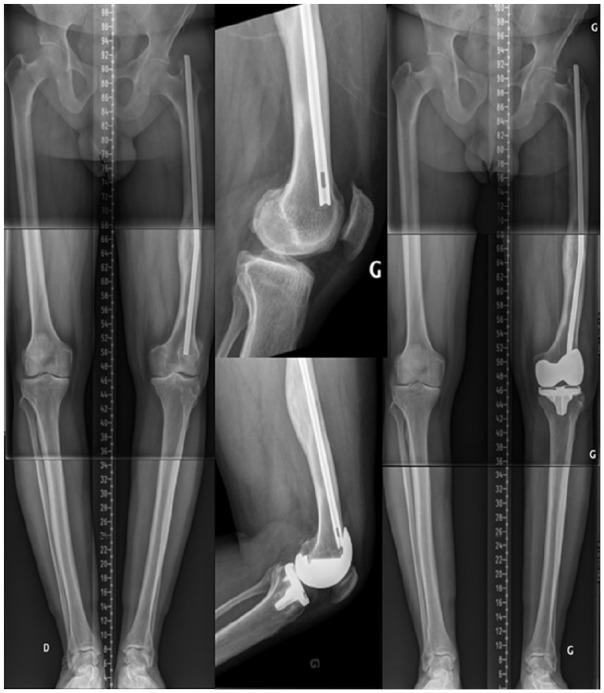

采用运动学对线技术植入全膝关节置换术(TKA)的具体病例考量。

Specific case consideration for implanting TKA with the Kinematic Alignment technique.

The Kinematic Alignment (KA) technique for total knee arthroplasty (TKA) is an alternative surgical technique aiming to resurface knee articular surfaces.The restricted KA (rKA) technique for TKA applies boundaries to the KA technique in order to avoid reproducing extreme constitutional limb/knee anatomies.The vast majority of TKA cases are straightforward and can be performed with KA in a standard (unrestricted) fashion.There are some specific situations where performing KA TKA may be more challenging (complex KA TKA cases) and surgical technique adaptations should be included.To secure good clinical outcomes, complex KA TKA cases must be preoperatively recognized, and planned accordingly.The proposed classification system describes six specific issues that must be considered when aiming for a KA TKA implantation.Specific recommendations for each situation type should improve the reliability of the prosthetic implantation to the benefit of the patient.The proposed classification system could contribute to the adoption of a common language within our orthopaedic community that would ease inter-surgeon communication and could benefit the teaching of the KA technique. This proposed classification system is not exhaustive and will certainly be improved over time. Cite this article: 2021;6:881-891. DOI: 10.1302/2058-5241.6.210042.

全膝关节置换术(TKA)的运动学对线(KA)技术是一种旨在对膝关节关节面进行表面置换的替代手术技术。TKA的受限KA(rKA)技术对KA技术应用了边界条件,以避免重现极端的肢体/膝关节解剖结构。绝大多数TKA病例较为简单,可以采用标准(非受限)方式的KA技术进行手术。在一些特定情况下,实施KA TKA可能更具挑战性(复杂KA TKA病例),应包括手术技术的调整。为确保良好的临床效果,复杂KA TKA病例必须在术前识别并进行相应规划。所提出的分类系统描述了在进行KA TKA植入时必须考虑的六个具体问题。针对每种情况类型的具体建议应提高假体植入的可靠性,从而使患者受益。所提出的分类系统有助于在我们的骨科领域采用一种通用语言,这将便于外科医生之间的交流,并可能有益于KA技术的教学。这个提出的分类系统并不详尽,肯定会随着时间的推移而改进。引用本文:2021;6:881 - 891。DOI:10.1302/2058 - 5241.6.210042。